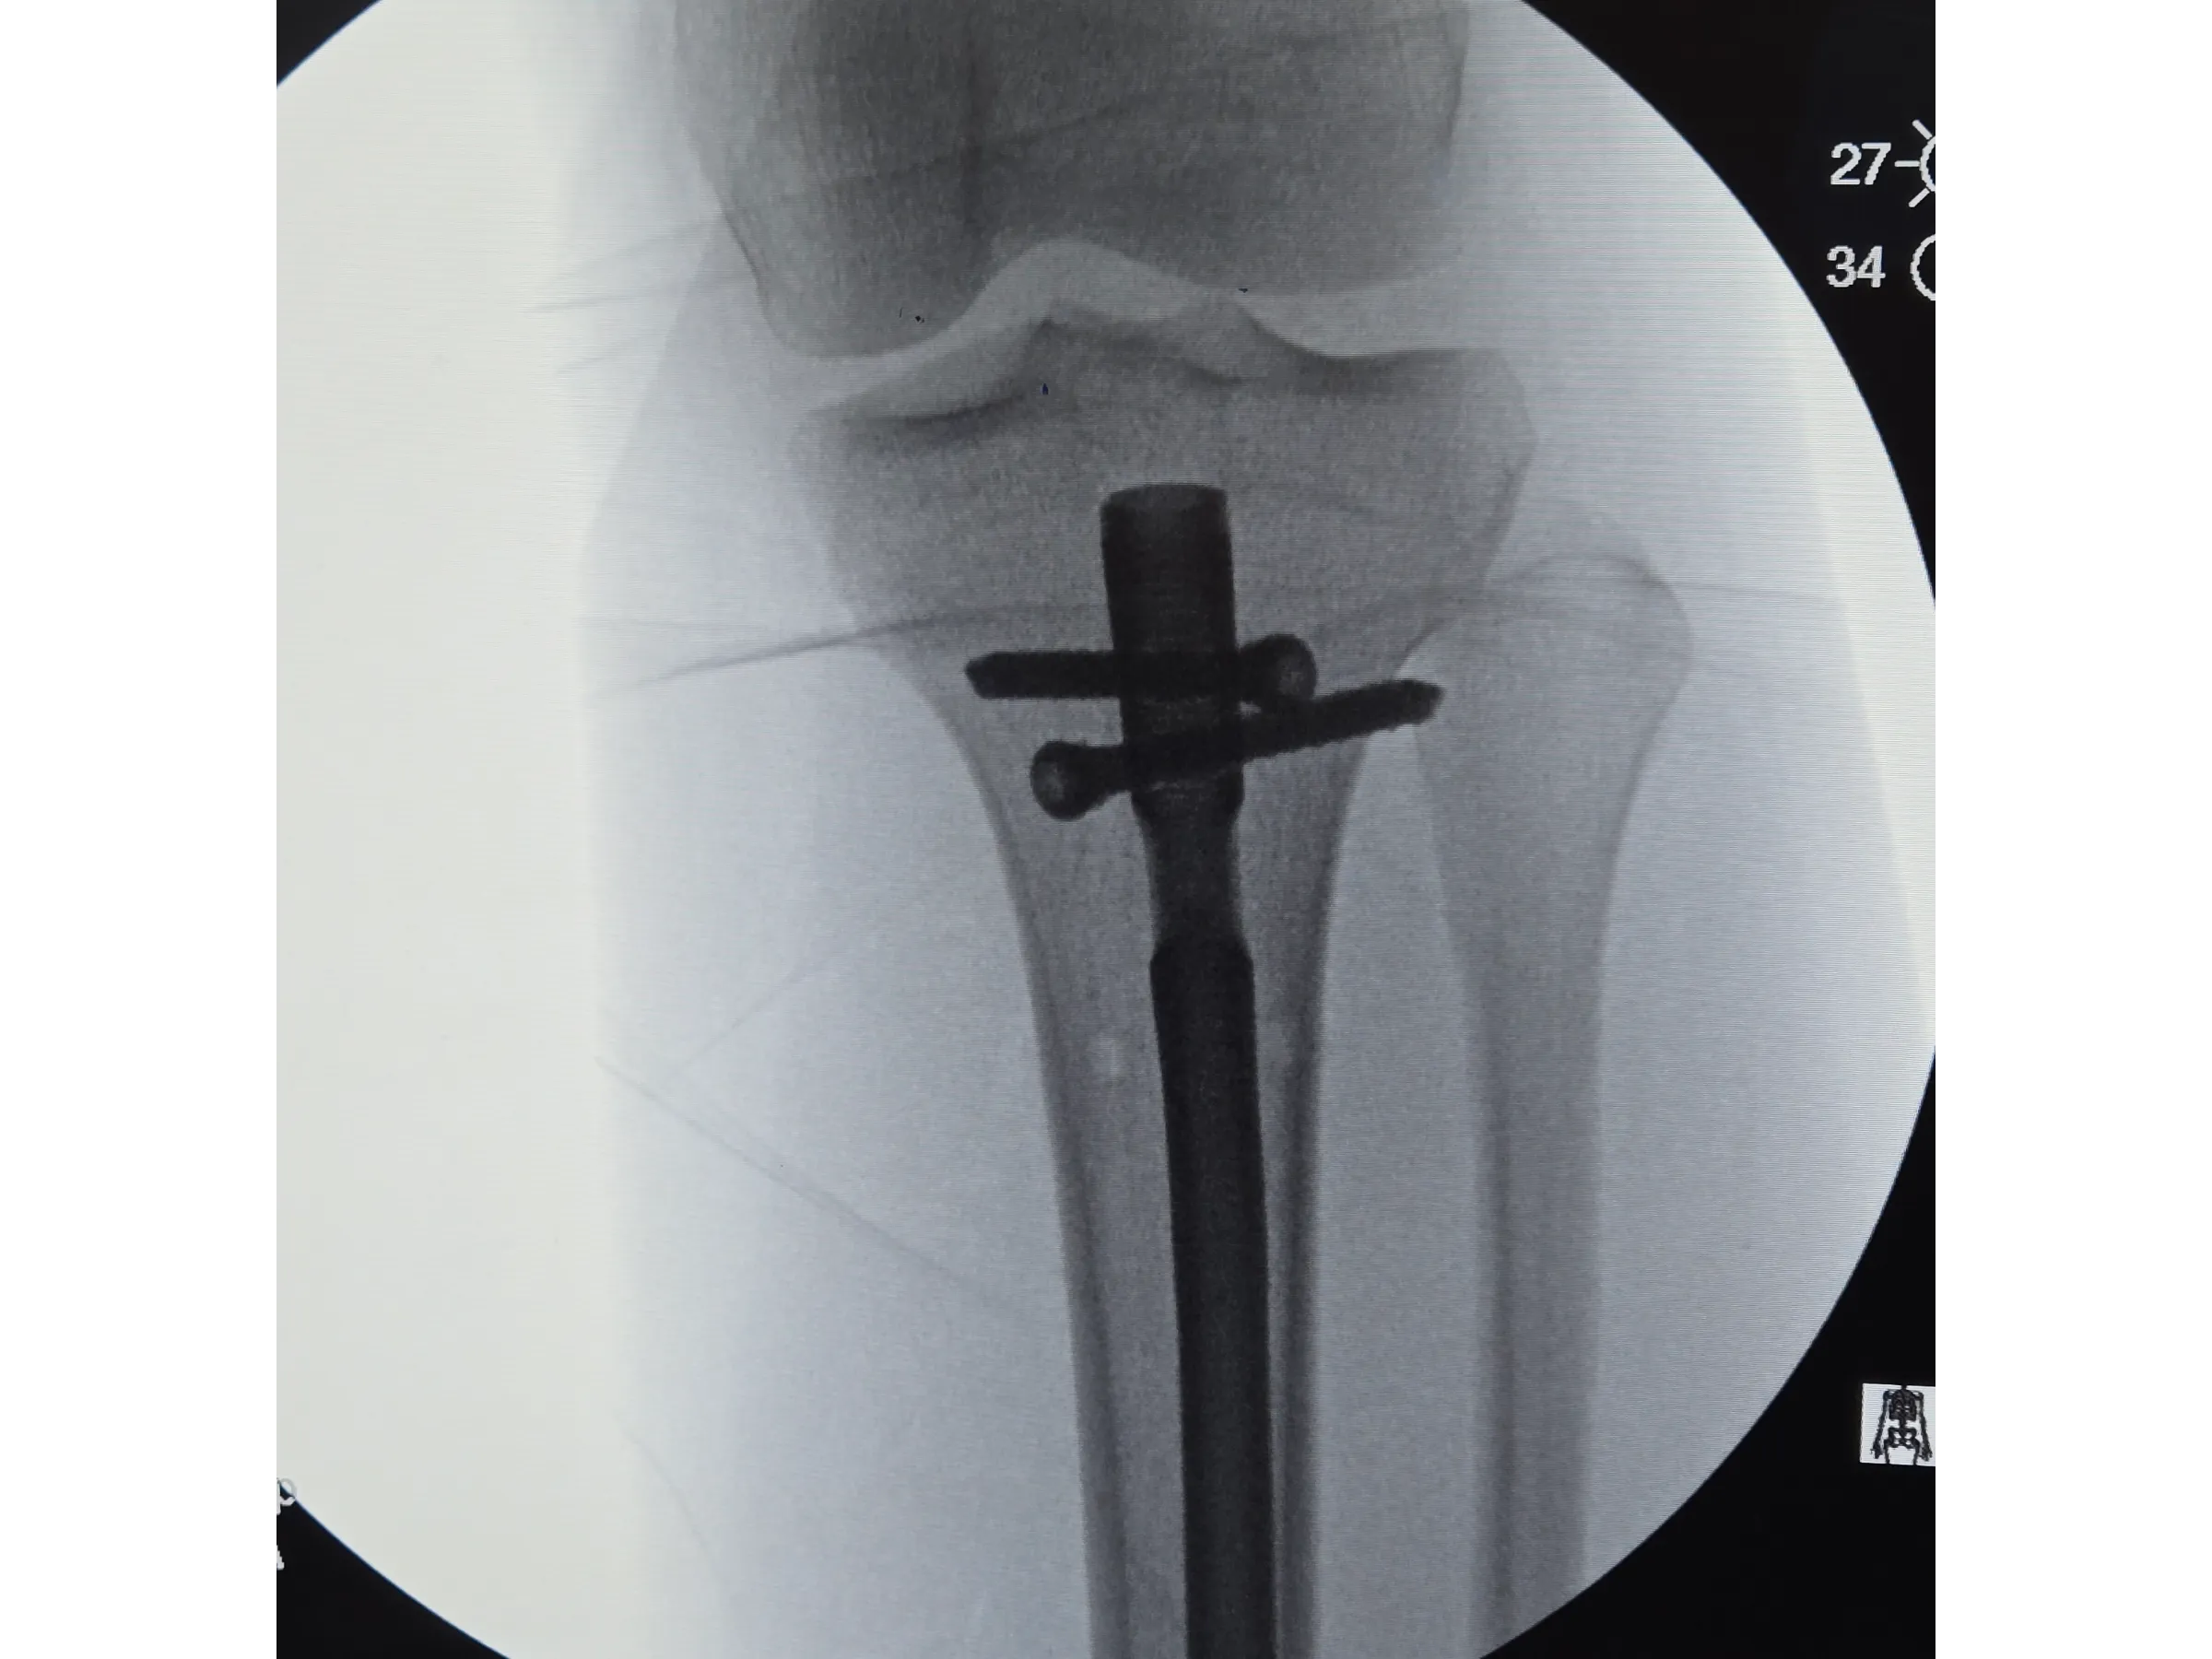

- Bloqueios proximais e distais com abordagem minimamente invasiva;

- Bloqueios Proximais e Distais Minimamente Invasivos: Execução de bloqueios cruzados e distais com pequenos portais e controle por intensificador;

- Avaliação Pós-Implante: Critérios para confirmar estabilidade, alinhamento e ausência de proeminência da haste.